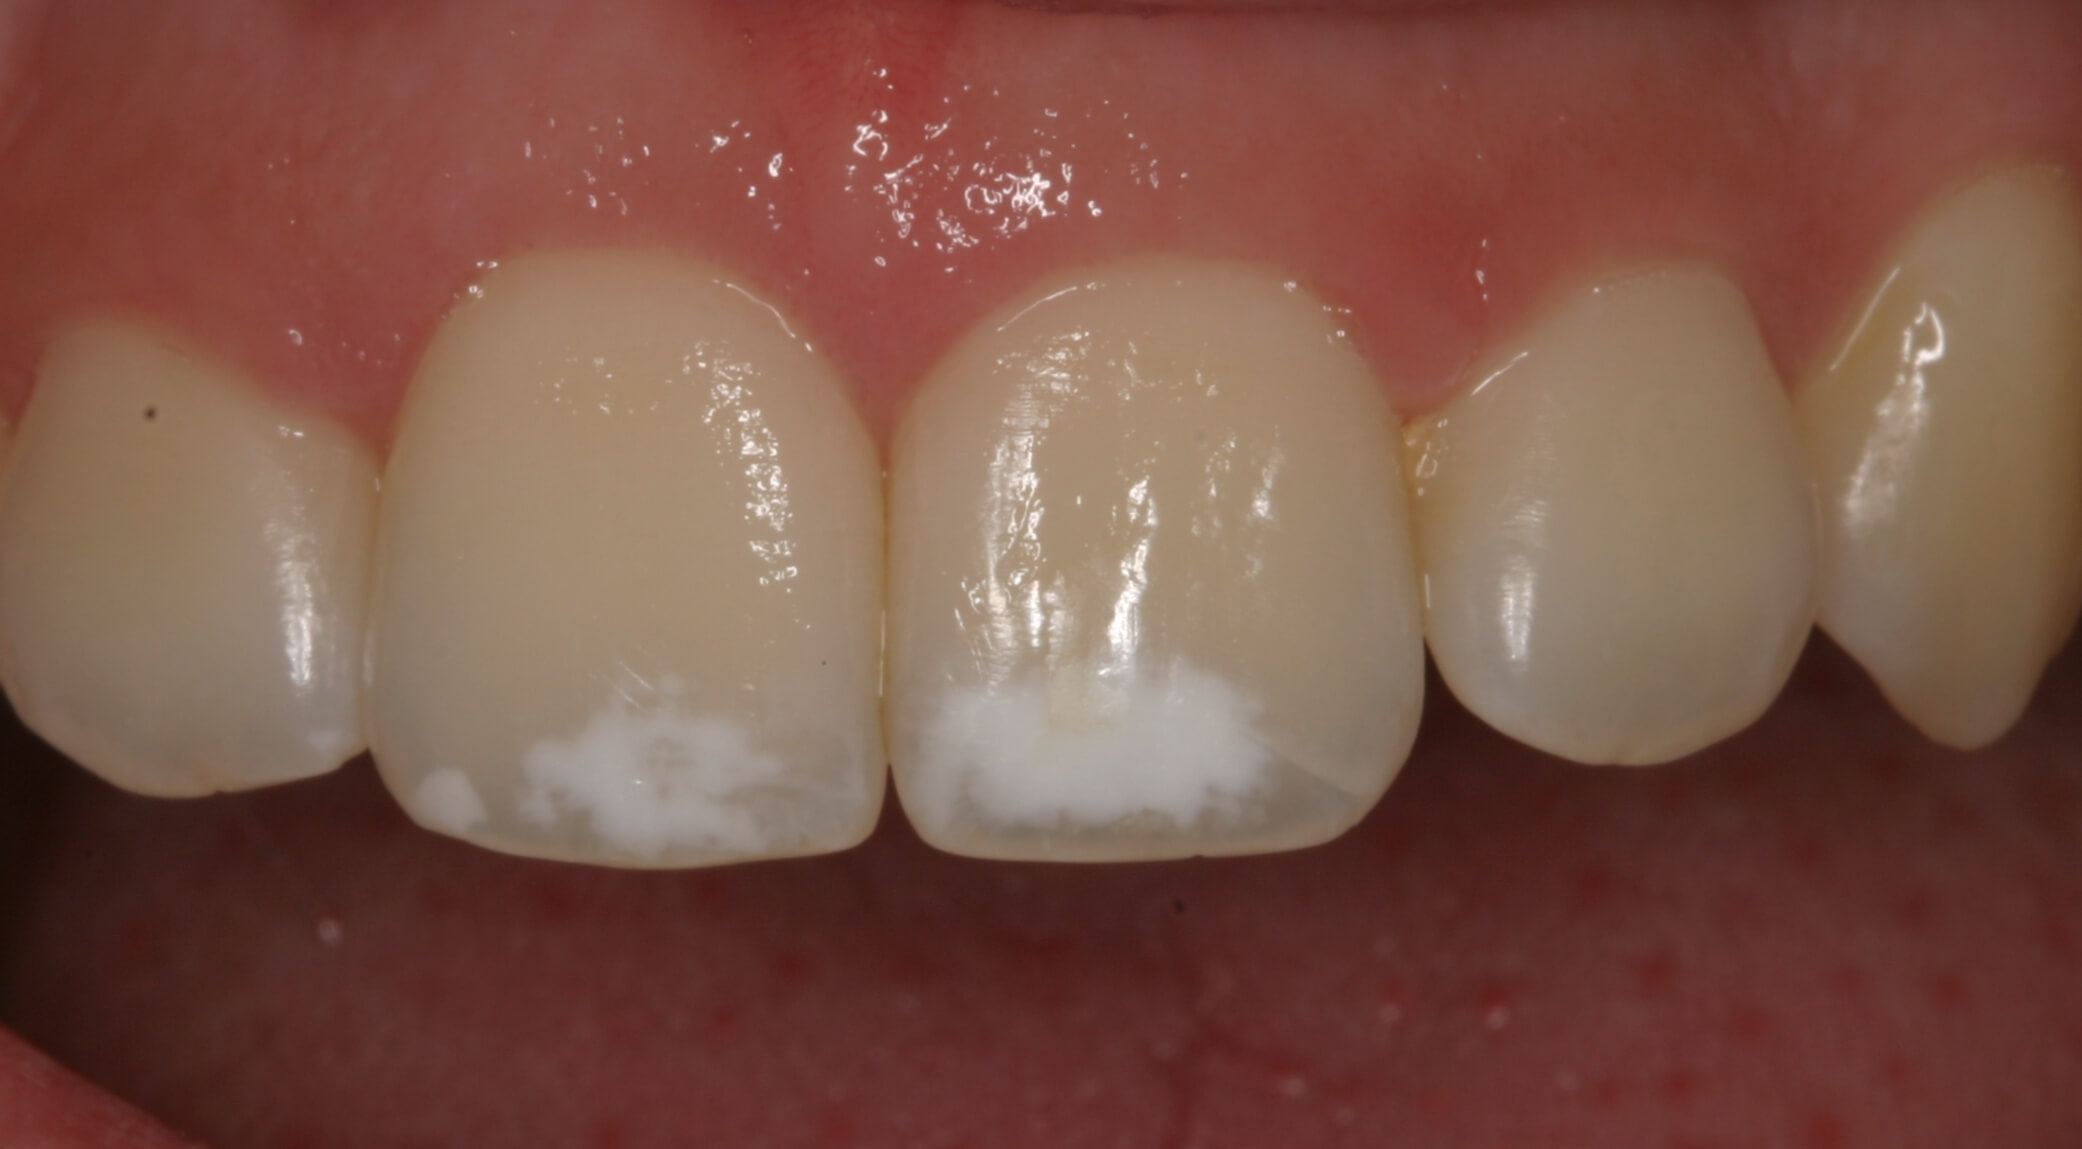

Pero en otros casos, son los papás los que notan las manifestaciones del problema en las piezas dentarias de sus pequeños. Pueden observarse manchas o puntos blancos, líneas, fisuras, hoyos, surcos o abolladuras en la superficie del esmalte. Además, la textura del defecto es áspera y opaca.

Existen casos en los que la hipoplasia dental en los niños se ve de color amarillento o amarronada, pues se descubre la dentina subyacente. Y en ocasiones más raras puede estar alterada la forma del diente. Incluso, cuando el trastorno es muy severo, puede haber una ausencia total del esmalte y los dientes lucen más chicos y deformes que los demás.